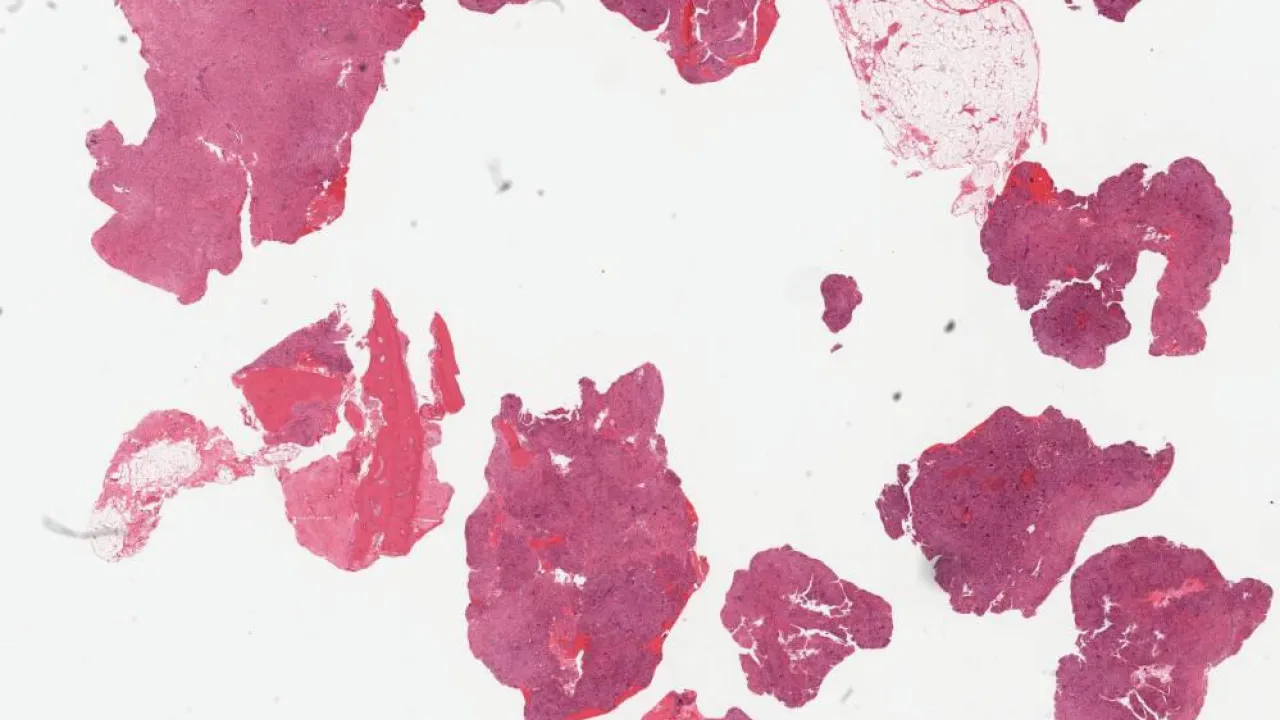

Soft Tissue, Angiolipoma